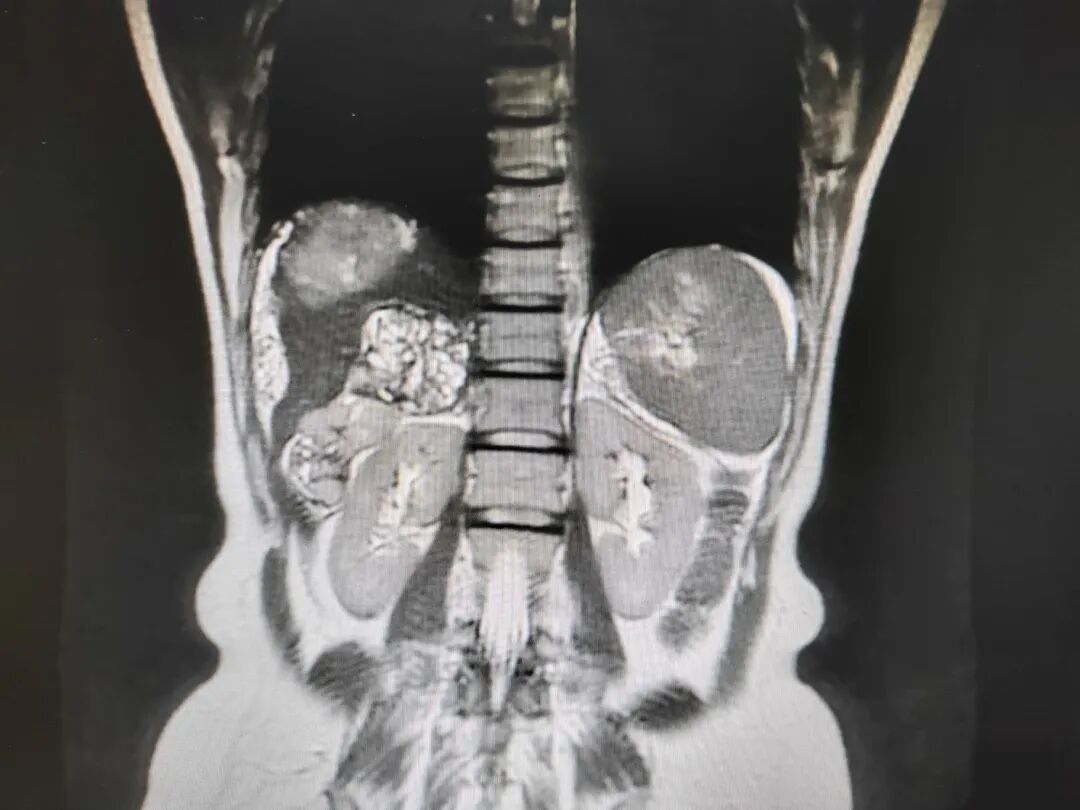

李晓光教授:复发肿瘤广泛分布于盆腹腔,大部分肿瘤可以切除,手术的真正难点在于肝门部肿瘤的切除,因为包绕门静脉等血管,手术风险极高,需肝胆外科专家协助手术。

车旭主任:肝周肿瘤累及肝门、第二肝门,紧邻门静脉、肝静脉等大血管,手术风险极大,如果妇科需要协助,肝胆外科将全力配合。

“进入腹腔就看见腹腔内血性液体,肿瘤出血,盆腹腔大大小小的肿瘤:膈顶、肝周、胆囊旁、肝门、肝肾隐窝、大网膜、肠管、肠系膜、膀胱表面、右侧卵巢、直肠窝、腹主动脉旁均可见肿瘤,肝周肿瘤广泛。”